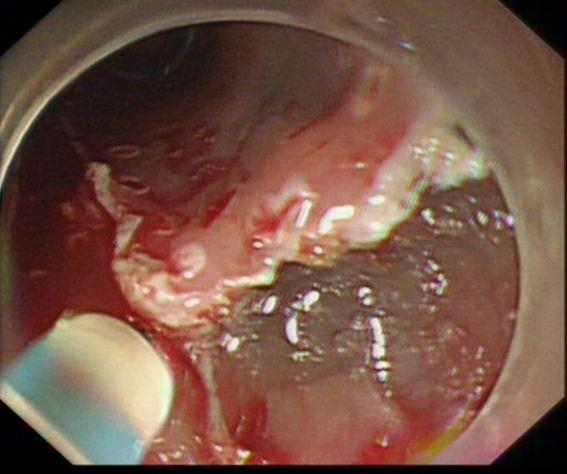

予Dual刀行黏膜下剥离

完整剥离病灶